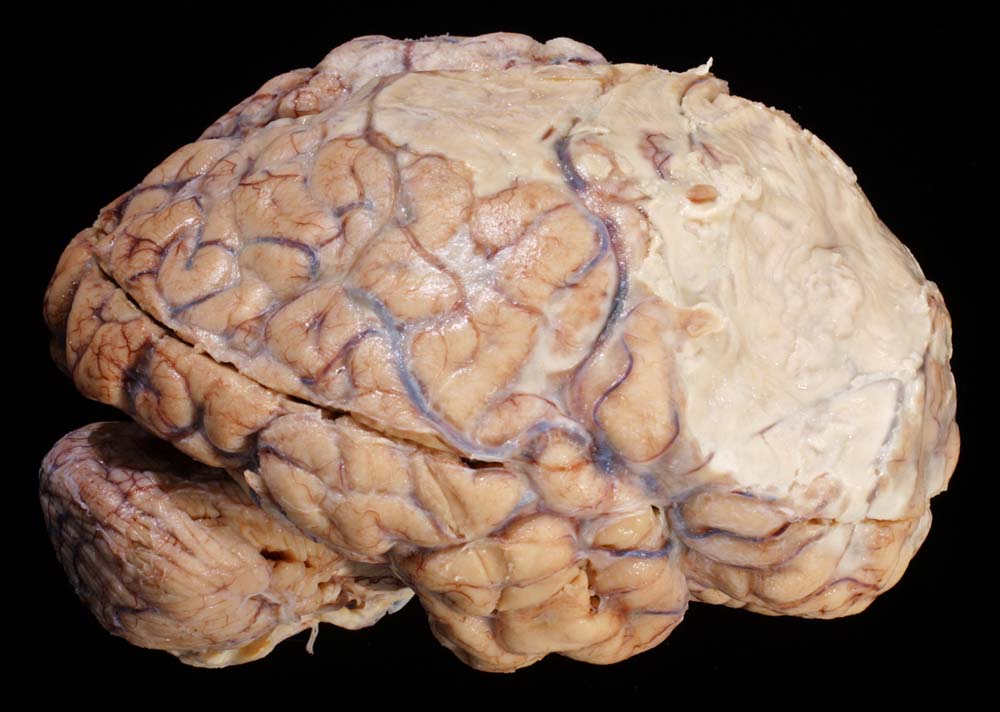

PathoPic – image database / PathoPic ID 8898 - Eitrige Meningoenzephalitis (Pneumokokken)

Eitrige Meningoenzephalitis (Pneumokokken)

Die rechte Hemisphäre ist bedeckt mit Eiter (subdurales Empyem).

Chronischer Alkoholabusus. Diabetes mellitus. Hospitalisation in somnolentem febrilem Zustand im Rahmen einer Pneumokokkensepsis. Klinisch Ausschluss einer Endokarditis. Ischämie rechts frontotemporal mit schlaffer Hemiparese links. Unklarer neurologischer Zustand vermutlich metabolisch-toxischer Genese. Rhabdomyolyse bei St.n. Liegetrauma. Niereninsuffizienz. Tracheotomie wegen respiratorischer Verschlechterung.